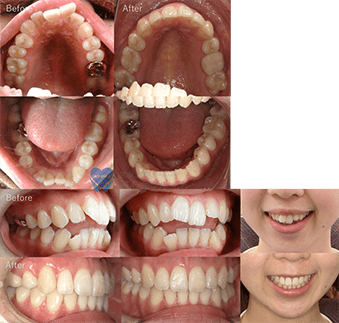

治療方法 床矯正で上下横に拡大しインビザラインへ移行、親知らず抜歯あり 治療の説明 主訴:叢生、

上下の前歯叢生が気になる年齢 26歳 ![]()

治療費用 877,800円(税込)

(インビザライン767,800円 床矯正2装置110,000円)治療期間 2年4カ月 通院回数 17回 治療の副作用(リスク) 元々隙間が開いていたところはしっかり保定装置を入れておかないと後戻りする可能性があります。咬合痛、歯根吸収、歯根露出が生じる可能性があります。 歯科医師からのコメント 元々上下の前歯が噛み合っておりませんでしたが、上の前歯を後ろに下げることで前歯のかみ合わせも良くなっています。